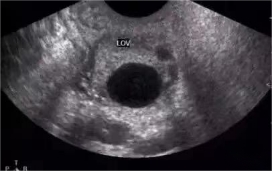

5.彩超监测卵泡发育情况

B超下能直观的看到卵泡发育大小,是否成熟,大约何时成熟,指导备孕夫妇更好的把握同房时机。